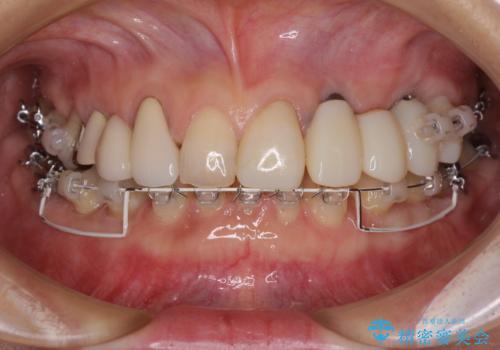

- 割れていると言われて放置してしまった歯や、前歯のデコボコなどが気になるとのことで来院された患者様です。

左上の歯は割れてしまっており、抜歯のうえインプラント治療が必要であり、他にも抜歯の必要な歯がある状態でした。

上顎はほぼ全ての歯をセラミッククラウンにて補綴治療を行う必要があるため、気になるデコボコや深い咬み合わせを改善するために下顎と上顎の臼歯部の矯正治療を行うこととしました。

並行して左下にはインプラントを埋入し、矯正治療を終えると同時に補綴治療を行うこととしました。

過蓋咬合(下顎前歯が隠れてしまうほどの深い咬み合わせ)のため、スムーズに歯が動かず矯正治療に時間がかかりましたが、無事に仕上げることができました。